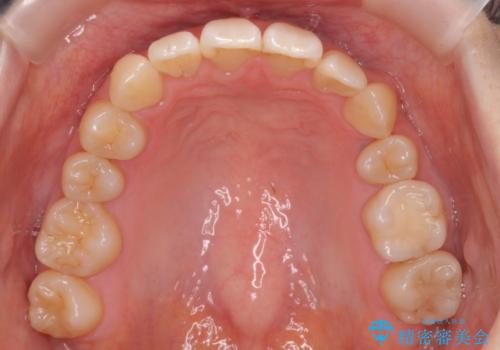

- 前歯のがたつきを主訴に来院。

下の前歯は生まれつき1本少ない状態でした。

左上の犬歯が入りきらずねじれており、かみ合わせもずれていました。

左上の小臼歯を1本抜いて治療しています。

前歯は内側に傾いており(ラビッティング)、過蓋咬合(深いかみ合わせ)を呈していました。

難しい治療でしたが綺麗に咬み合わせることができ、また前歯もしっかり当たるように治療できました。